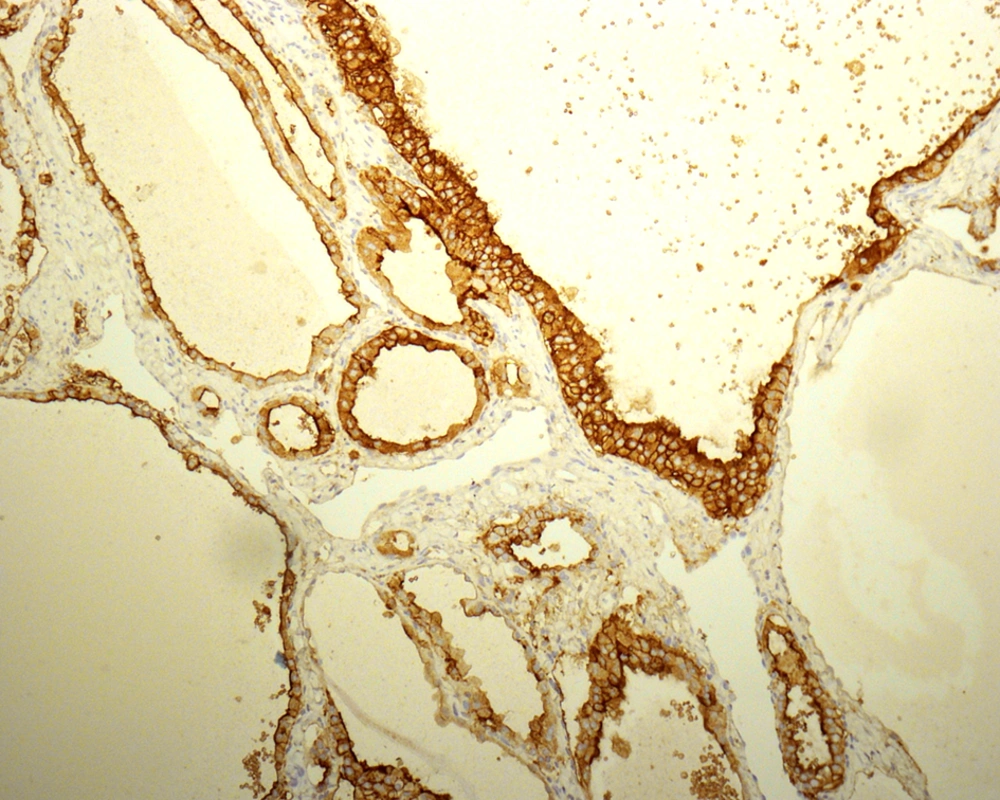

The absence of strict and uniform criteria among expert pathologists, particularly in difficult cases, results in the use of terms such as “multifocal PTC arising in a benign nodule” and “follicular tumor of uncertain malignant potential”. Therefore, there is controversy regarding reporting the cytohistologic condition of these lesions (27, 29-31) and a range of proposals have been made to clarify this issue. LiVolsi and Baloch preferred a scheme in which a diagnosis of MFVPTC would be made on any encapsulated lesion showing any area with the characteristic cytologic features of PTC (32). Chan suggested using stricter criteria including the evaluation of major and minor features. Some immunohistochemical markers, such as high-molecular-weight cytokeratin, cytokeratin 19, vimentin, HBME1 (Figure 5), CD57, CD15, and CD44 have been reported to be more commonly expressed in PTCs than in benign thyroid lesions. These markers are not sufficiently discriminatory to aid in the diagnosis of problematic encapsulated follicular lesions of the thyroid (31).